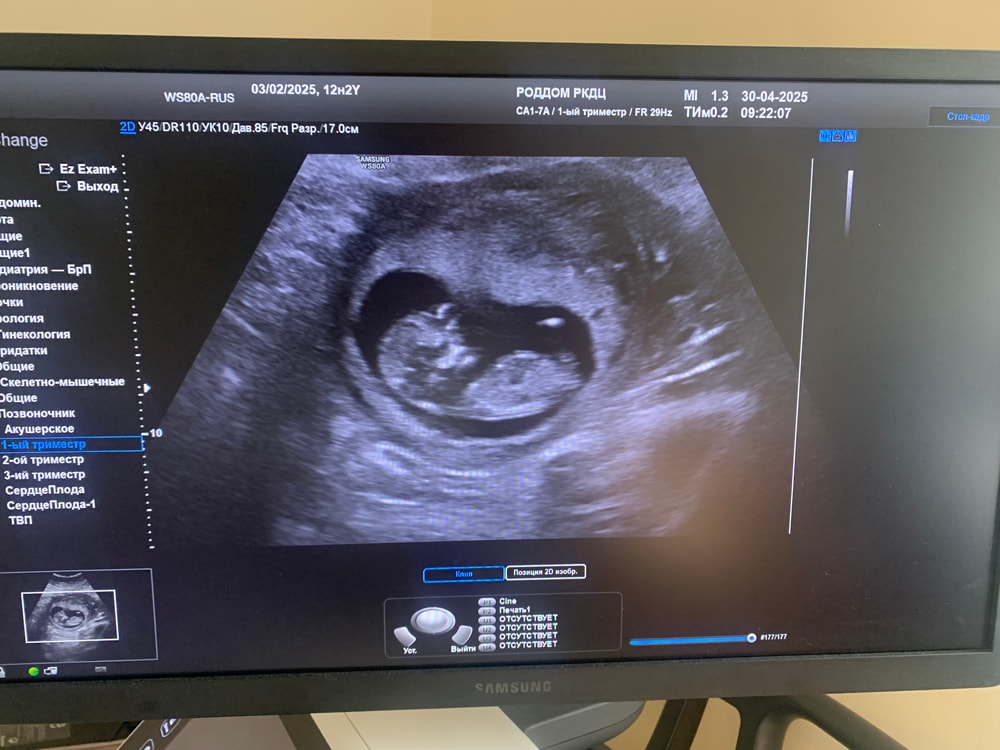

13я неделя. 1 скрининг. УЗИ 😍

УЗИ, КТГ, доплерВсем привет. Сегодня ходила на УЗИ и сдала кровь. Кто обладает зорким взглядом, кто же это: мальчик или девочка? 🥹

Малыш развивается по сроку. КТР 56 мм, бипариентальный размер 17 мм, окружность головы 62 мм. Ручки ножки, внутренние органы все в норме. Толщина ТВП 1,6, носовая кость определяется. По УЗИ врожденных пороков развития не обнаружено 🥳 Прикрепление к передней стенке, животик уже видно, пришлось оперативно обновлять гардероб 😄